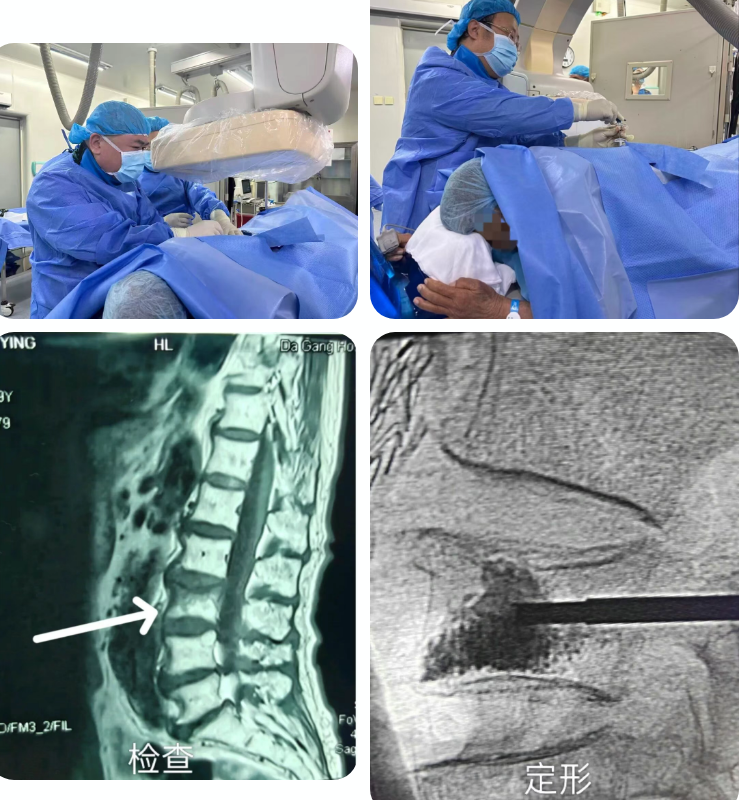

为确保手术安全,科室启动多学科协作机制,联合麻醉科、放射影像科进行术前会诊,共同制定个体化麻醉方案与精准影像引导路径。手术在基础麻醉和局部麻醉下进行,在实时影像引导下,医生经皮穿刺建立微小通道,将球囊精准置入压缩的腰三椎体内,并缓慢扩张球囊复位椎体,随后注入骨水泥强化椎体稳定性。手术创口微小,过程顺利,术中出血少、耗时短,患者未出现任何并发症,真正实现“微创、精准、安全”。